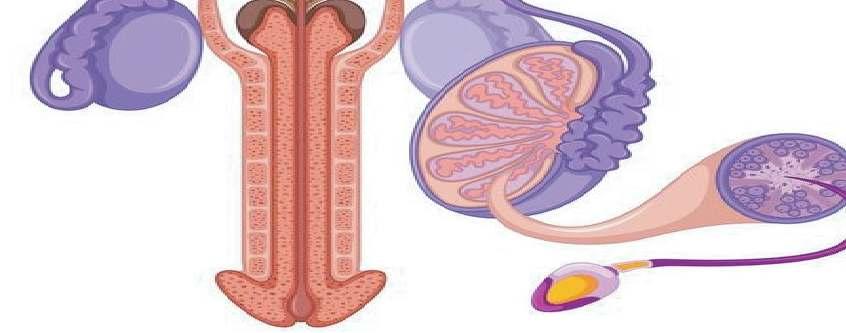

ASPECTOS BIOLOGICOS DE LA REPRODUCCIÓN HUMANA

Desde el nacimiento del ser humano claramente definidos sus organos sexuales (caracteres sexuales primarios). Con el trascurso de los años, al llegar a la pubertad el hipotálamo atúa sobre glándula hipófisis dando lugar a que las hormonas actúen tanto en los testículos en el caso de los hombre y los ovarios en caso de las mujeres llevando acabo la produccuón de espermatozoides y de hormonas. Su función se haxe evi dente durante el coito o la masturba ción, en los cuales representan variaciones en tamaño y posición de acuerdo a los niveles de exi tación.

Un aspecto importante de la biología de la reproducción humana es la forma en que los procesos mencionados inciden en la aparición de patologías reproductivas.

La biología de la reproducción también estudia los mecanismos que regulan la diferenciación sexual; la efectividad, efectos adversos y dosificación de agentes farmacológicos utilizados en la regula ción de la fertilidad.

ANATOMÍA GENITAL MASCULINA

Durante la excitación sexual los espermatozoides salen del epidídimo a través del conducto deferente. Allí se mezclan con el líquido producido en las vesículas seminales y la próstata para formar el semen.

Hay que destacar que el semen ayuda a nutrir a los espermatozoides y a la vez ha transportarlos

* La uretra: Esta transporta orina y semen. Durante el orgasmo el semen se eyacula por la uretra.

* Los testiculos: Son glándulas que producen espermatozoides y a la vez producen hormonas son células reproductoras.

* El epididimo: Este es un conducto enrollado que alberga a los espermatozoides mientras maduran.

* El conducto deferente: Transporta el esperma desde el epidídimo hasta el pene.